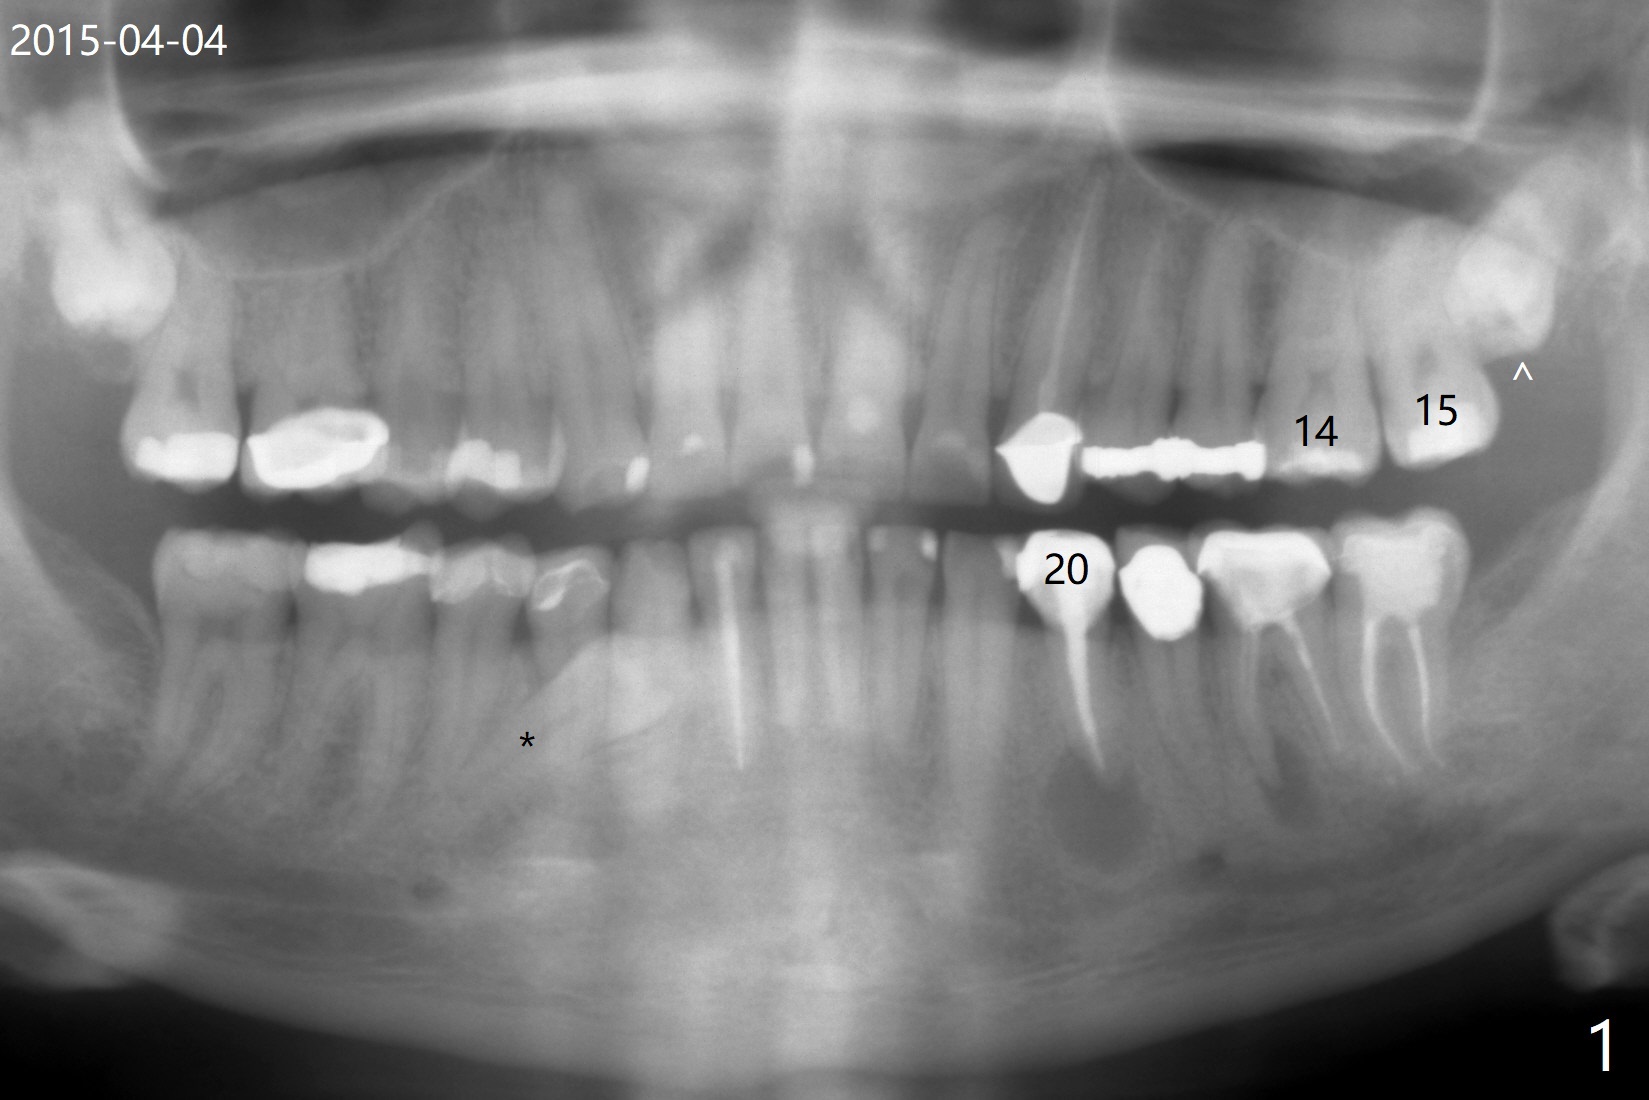

A 37-year-old man complains of food impaction between #14 and 15, which may be related to mesioangular impaction of #16 (Fig.1 ^ (* a supernumerary premolar; #20 asymptomatic after RCT retreatment)). When the third tooth is removed, it is smaller than expected. Intraop X-ray reveals a normal sized 3rd molar in situ (Fig.2 ^). Therefore the microdontia removed is a supernumerary tooth. The tooth #16 is then extracted. The diastema appears to persist 2 years 7 months postop (Fig.3), although gingival swelling and pain reduces. There is a significant increase in PARL at #20, supported by 2 PAs (Fig.4,5). The tooth has no mobility with normal periodontal pockets. There is no paresthesia of the lower left lip.